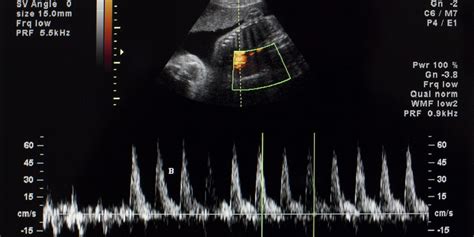

Come tutti gli esami ecografici, per esempio l’ecocardiocolordoppler, anche l’ecocardiografia utilizza gli ultrasuoni, onde sonore ad alta frequenza che colpiscono le strutture cardiache del feto e rimbalzano, tornando al macchinario che le rileva. Grazie all’ecocardiogramma, quindi, verranno evidenziate le camere cave del cuore, gli atri e i ventricoli, responsabili del riempimento di sangue, i setti, le strutture fibrose che separano le camere cardiache, le valvole, strutture che direzionano il flusso di sangue ed evitano che fluisca all’indietro.

L’ecocardiografia fetale fornisce informazioni anche sulla direzione e la velocità del flusso sanguigno attraverso il cuore. In particolare, in un’ecografia color Doppler, frequenze diverse degli ultrasuoni corrispondono a diversi colori sull’immagine ecografica. Questi colori, che variano dal blu al rosso, mostrano la velocità e la direzione del flusso sanguigno in tempo reale. L’esecuzione e l’interpretazione dell’ecocardiografia fetale richiedono un insieme unico di abilità e conoscenze avanzate. Il cuore fetale, infatti, è di piccole dimensioni e di natura molto dinamica.

- Mediante il color doppler vengono poi indagate le modalità e la direzione del flusso nelle cavità cardiache e misurate le velocità con il Doppler spettrale ove necessario.